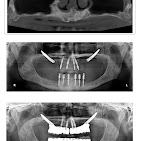

We provide comprehensive dental care using modern techniques and advanced technologies. Whether you'... re looking for braces, cosmetic smile corrections, or full-mouth implants, our team delivers precise, comfortable, and long-lasting treatments that restore confidence and oral health. Your smile is in safe hands with our expert dental care professionals. Read more